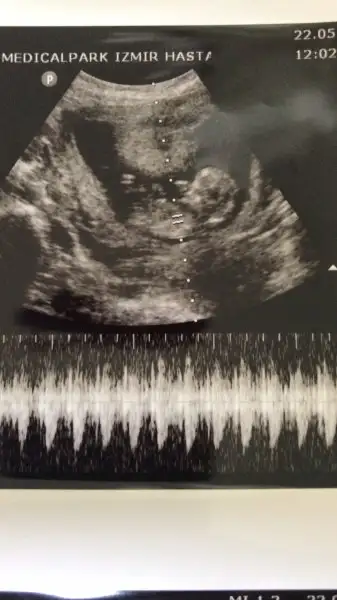

Erkek gibi dedi ama 16 haftayı bekliyorum cnmBenimkine benziyor bakalım belli olunca söyler misin bana daha cok var belli olmasına

Cnm nub teorisi diye arastır istersen bir orda daha net belki fikrin olur allah gönlündekini versin inş ama sanırım bu 2018 de herkes daha bir kız istiyor ben de dahil sağlıklı olsunlar daBenim ki kız mu erkek mi?

Teşekkür ederim sonra gördüm oraya da ekledim. Evet benim iki erkekten sonra bir kız istemem çok doğal umarım Allah gönlümüze göre verirCnm nub teorisi diye arastır istersen bir orda daha net belki fikrin olur allah gönlündekini versin inş ama sanırım bu 2018 de herkes daha bir kız istiyor ben de dahil sağlıklı olsunlar da